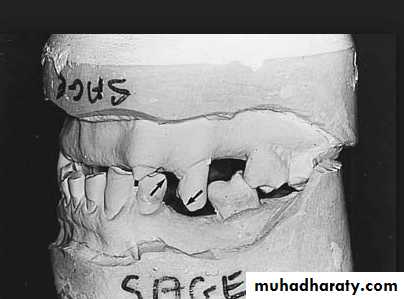

Evaluation of mounted diagnostic casts

Potential problems such as insufficient inter arch distance, irregularity or mal position of the occlusal plane, extruded or malposed teeth, and unfavorable maxillomandibular relationships are more apparent in accurately mounted casts because the lips, cheeks, and skull block out good visual access to the teeth in the mouth.4/2/2018

Interarch space

Lack of sufficient inter-arch distance- difficult for placing the teethFrequently it is caused by maxillary tuberosity that is too large in vertical height- surgical reduction vertical height is necessary for satisfactory replacement of the missing teeth.

Tipped or malposed teeth

Limited orthodontic procedures for minor tooth movement can be used to upright the tipped tooth to allow the placement of an artificial tooth of more normal size.Orthodontic appliances, rubber ligature used to correct the position